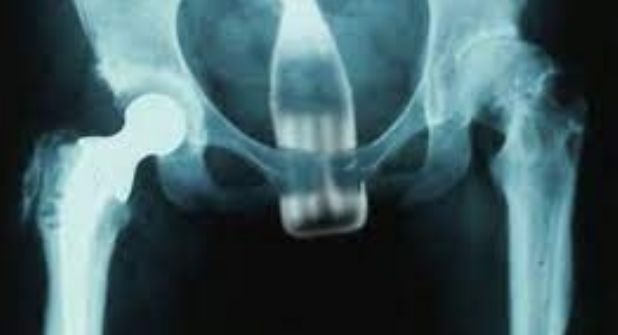

Inmediatamente después de que contara lo ocurrido, procedieron a realizarle unos estudios de rayos X, y ahí fue cuando constataron que efectivamente el objeto estaba alojado en su parte posterior.

Tras el diagnóstico, el paciente fue atendido en el Hospital Central de Maracay, a unos seis kilómetros de la clínica inicial.

El paciente fue sometido a una cirugía de emergencia, ya que en algunos casos, los objetos extraños que se atascan en el recto están lo suficientemente cerca del ano, como para extraerlos con la mano, aunque pueden presentarse problemas debido a que existe una fuerte succión entre el objeto y las paredes del recto.

Durante el procedimiento es probable que el médico pase un tubo entre el objeto y la pared del recto para tratar de igualar la presión a medida que se extrae el objeto, lo cual es un procedimiento incómodo que requiere sedación, aunque si el objeto es demasiado profundo, es posible que se deba realizar una operación completa.